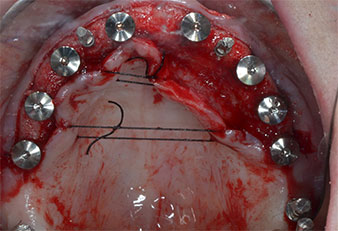

Fig. 1: Vista preoperatoria del borde maxilar, con las posiciones del implante marcadas con la ayuda de una plantilla quirúrgica de plástico. Debido a la baja altura del borde, se planificaron implantes posteriores supercortos.

Fig. 2: Después de la incisión en la zona crestal media y de la preparación de colgajos mucoperiósticos, las posiciones del implante se transfirieron al hueso.